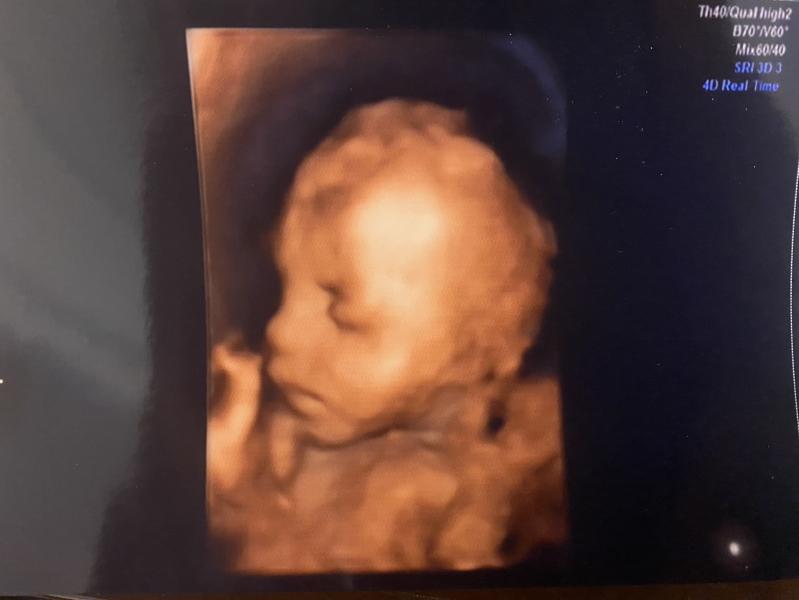

Какая же красивая у меня девочка 😍❤️

На узи сказали, что все прекрасно, только сидит на попе еще. Но ничего, время есть еще перевернуться.

На экране дочь мне и улыбалась и хмурилась и прыгала и ноги узлом завязывала)